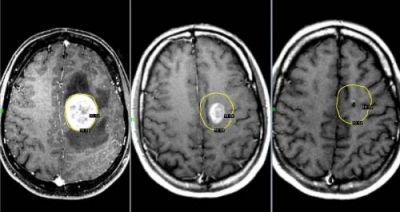

Рак мозга

При онкологическом заболевании мозга головная боль не всегда присутствует. Если она возникает, это свидетельствует о тяжелом течении болезни.

Головная боль, вызванная опухолью, возникает из-за повышения внутричерепного давления. Чем быстрее растет опухоль, тем выше давление.

Дискомфорт чаще всего ощущается утром и почти всегда сопровождается рвотой.

С прогрессированием заболевания частота и интенсивность болевых приступов увеличиваются.

Это может привести к потере веса и появлению судорог. При наличии симптомов рака мозга необходимо немедленно обратиться к онкологу.

Ранняя диагностика заболевания повышает шансы на выздоровление. Однако при поздней диагностике вероятность успешного удаления злокачественной опухоли значительно снижается.

Опухоли мозга

Это новообразования, локализующиеся в тканях мозга. Они могут быть доброкачественными или злокачественными. Доброкачественные опухоли не метастазируют, имеют четкие границы роста и могут лечиться безоперационным путем, не вызывая рецидивов.

Злокачественные опухоли быстро прорастают в окружающие ткани и могут образовывать метастазы в нескольких участках мозга.

Такие опухоли плохо поддаются лечению, и на поздних стадиях их развития спасти пациента практически невозможно.

Болевые ощущения постоянные и со временем усиливаются. При движении боль усиливается. Сначала она локализуется в области опухоли, затем, по мере увеличения внутричерепного давления, распространяется на лобную и затылочную части. Наиболее сильный дискомфорт ощущается ночью и утром из-за скопления жидкости. Вены не справляются с оттоком крови, что приводит к отечности и застойным явлениям. Боли могут быть давящими, распирающими или пульсирующими.

К головным болям добавляется рвота. Физическая нагрузка или кашель усиливают болевые ощущения, могут возникать двоение в глазах и временная потеря зрения. У пациента наблюдается головокружение и нарушение координации движений. Возможна онемение конечностей и ослабление мышечного тонуса.

Иногда возникают эпилептические припадки, возможна путаница в сознании.

Для диагностики применяются МРТ, ПЭТ, КТ мозга, ангиография и другие методы.